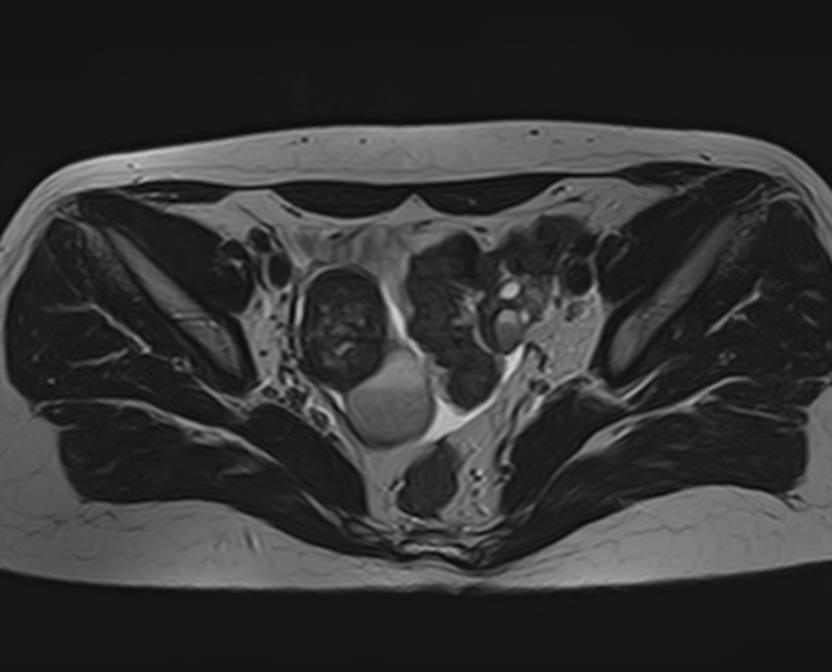

МРТ яичников: что показывает процедура

• Апоплексию яичника (разрыв придатка, сопровождающийся попаданием крови в брюшную полость и сильным болевым синдромом);

• Новообразования яичников (кисты, фибромы, рак);

• Признаки доброкачественного или злокачественного характера опухоли;

• Врожденные аномалии развития придатков;

• Признаки синдрома поликистозных яичников;

• Вовлеченность в опухолевый процесс соседних органов.